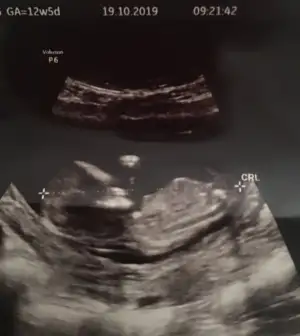

dr soylemeden siz gorun genital nub teorisi ( bebegin cinsiyeti)

Doktor kız tahmininde bulundu ama her gören erkek diyor :)

Evet erkek gibi iri bebek nubta tam dik değil kız yazacaktım .keşke görünüşüne bakmasaymışım 😂😂 saglıkla gelsin prenses 😍

Doktor tam kesin 3 hafta sonra söyleyecekmiş inşallah doktorun tahmini değişmez :)

Önceliğim sağlıklı olması ama kız deyince hemen alışıverdim :))

Oğlumu da 16. Haftada öğrenmiştim öncesinde hiçbir doktor tahminde bulunmamıştı . Bu doktorun kendisi dedi tahminde bulunaym mı dye , ben erken olduğunu düşndüğm için söylemesini istemiyodm ama öyle sorunca da söyleyin dedm :)